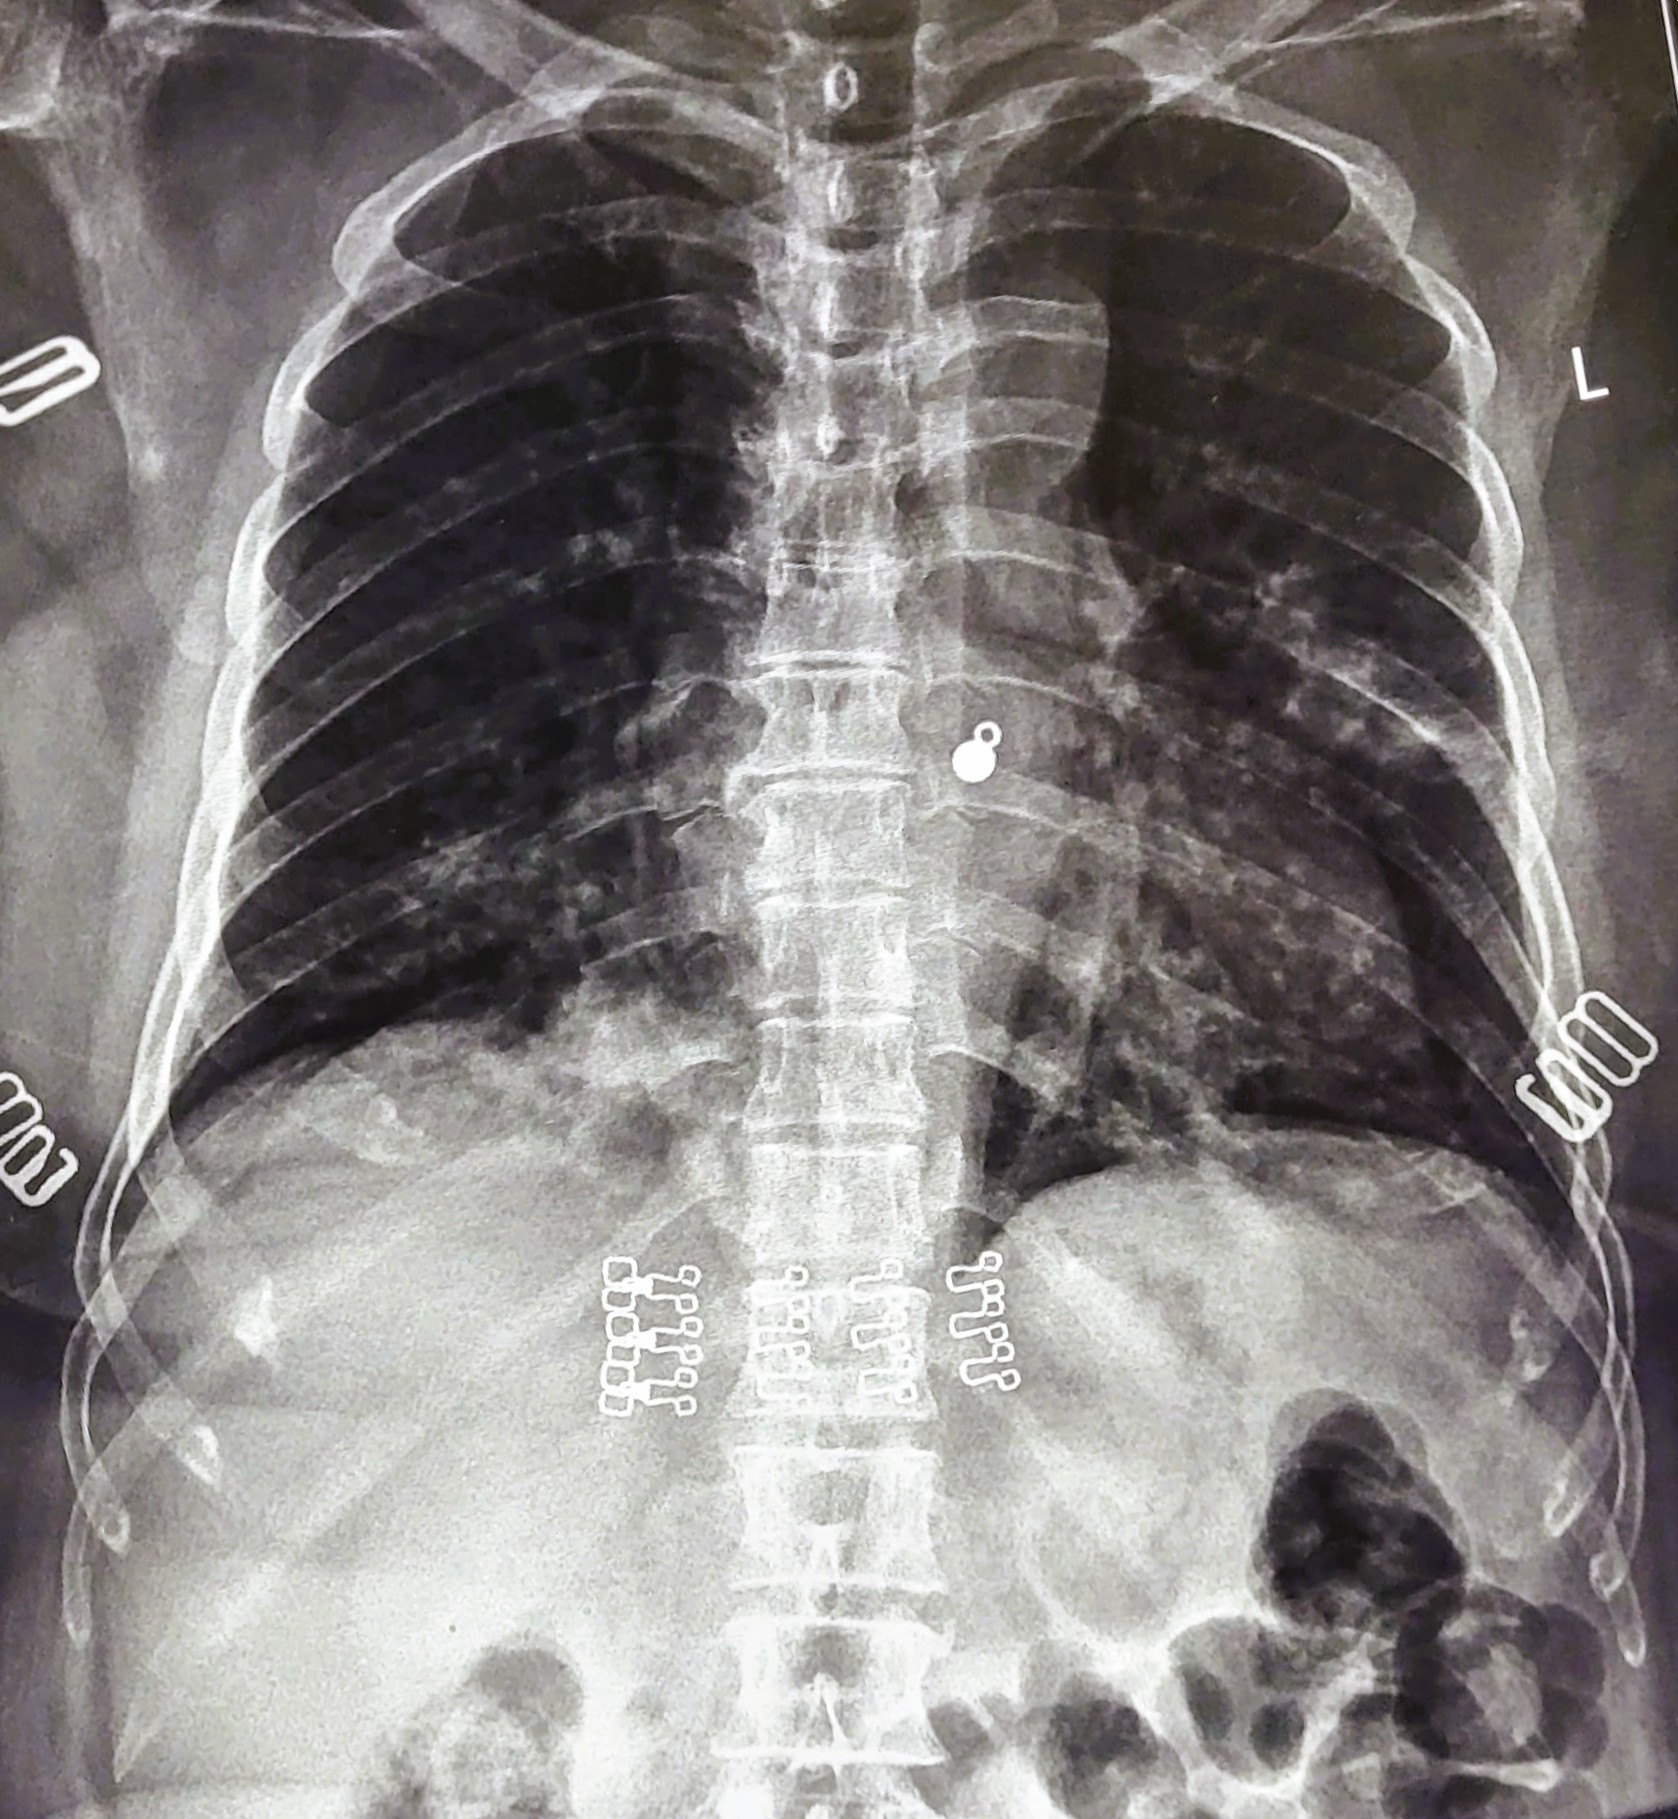

| 220 | IGGMC, Nagpur, Nagpur | P2 | 29-4252 | AMOL PAUNIKAR | Consent taken on Paper | 36 Yrs. |

Provisional Diag : BILATERAL INFILTRATION ? MILLIARY TB

Final Diag : MILLIARY TB |

TB Case (Confirmed) | MILLIARY TB | Abnormality visible on x-ray |

View |